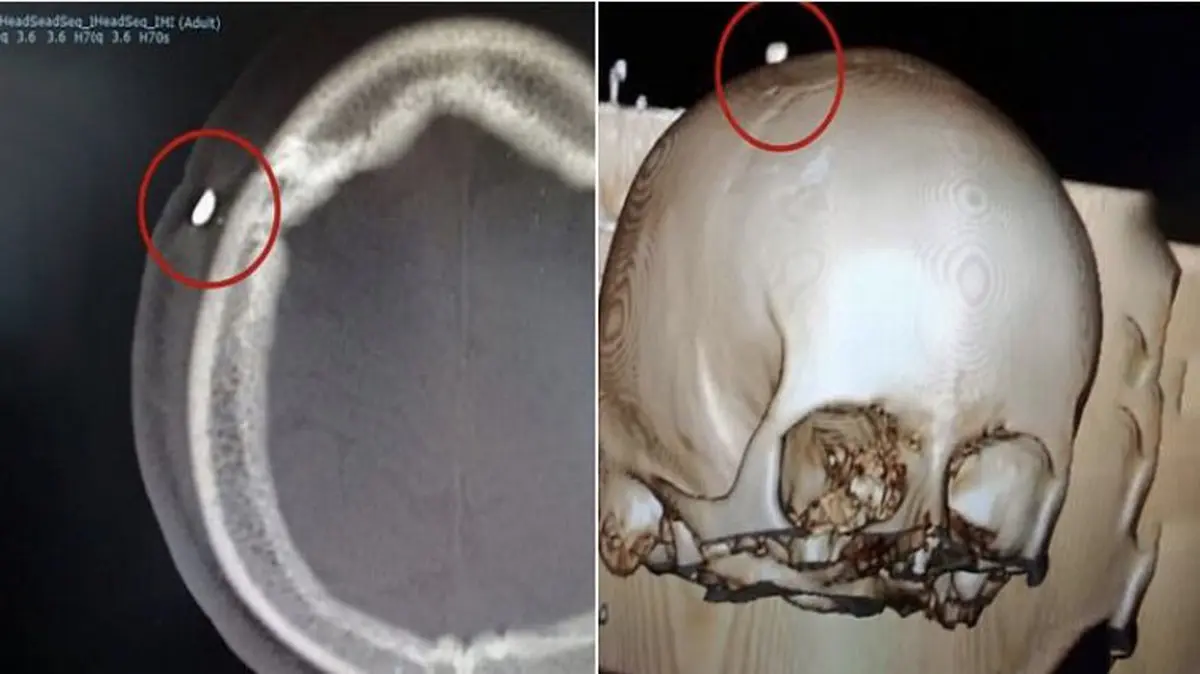

به گزارش گروه ترجمه رکنا، یک دندان از جمجمه پسر 14 ساله پرتغالی خارج شد.

بنا به گفته پزشکان، چندی پیش این پسر توسط فردی دیگر در بازی فوتبال گاز گرفته شد و به دلیل یک زخم 5 سانتی متری در سمت راست سرش به بیمارستان مراجعه کرد.

بیمار پس از بهبود در بیمارستان به خانه اش بازگشت اما پس از 5روز به دلیل تب و خواب آلودگی و چرک و عفونت در ناحیه سرش مجدد به بیمارستان رفت که پزشکان با مشاهده تورم روی سر بیمار او را بستری کردند و پس از سی تی اسکن متوجه دندانی در جمجمه وی شدند.

به گفته پزشکان این عمل جراحی بسیار دشوار بود اما آن ها توانستند دندان را خارج کنند .